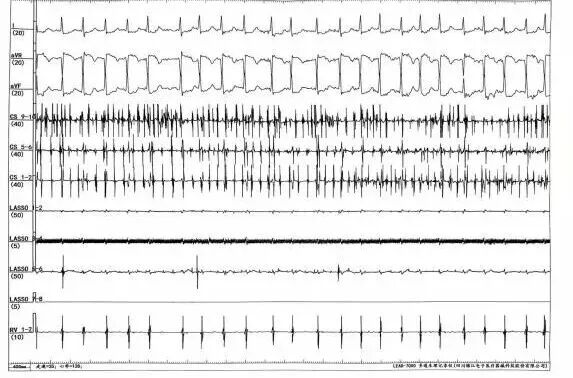

术前将DSA显示系统调整为180°镜像模式。术中,局部麻醉下建立股静脉通路,右侧置入2极和可调弯10极,左侧置入房间隔穿刺系统,通过造影剂确认房间隔穿刺成功,保留导丝置换冷冻球囊系统到左房,依次对左上、左下、右上、右下肺静脉进行冷冻消融,在冷冻至右上肺静脉过程中,转为窦性心律,四根肺静脉房颤相关电位脱落明确,起搏验证确定双侧肺静脉电位隔离,手术顺利完成。

术中肺静脉电位脱落图及腔内心电图转为窦性心律图